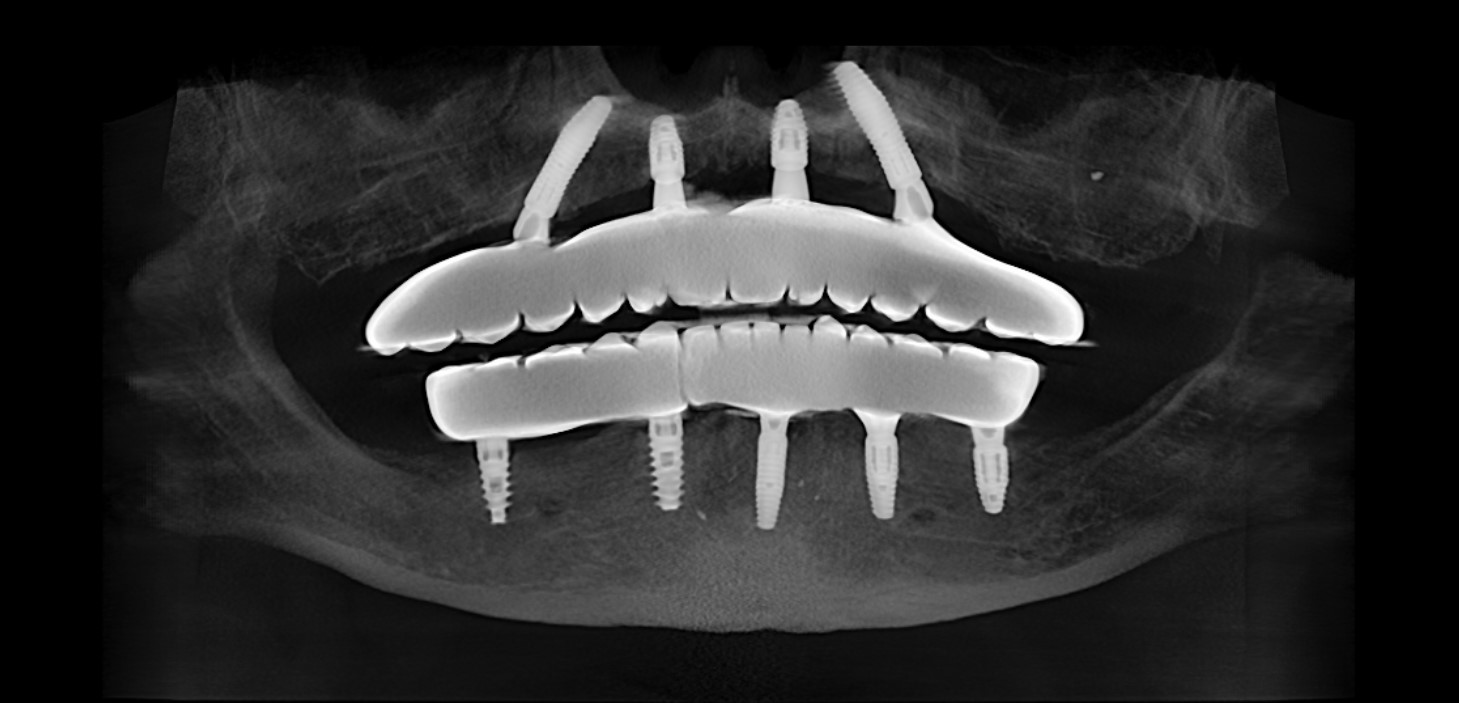

Одним из таких решений является тотальная имплантация с опорой на 4/6 имплантатов – международный протокол, известный как «All-on-4/6».

Современные имплантационные протоколы позволяют установить от 4 до 6 имплантатов на челюсть и создать на них надежную основу для несъемной конструкции, полностью восстанавливающей функцию и эстетику улыбки.

Перед операцией проводится компьютерная томография, после чего будущая улыбка моделируется в цифровой среде. Врач заранее планирует положение имплантатов, учитывая анатомию кости, распределение нагрузки и форму будущих зубов.

На основе этого плана изготавливаются специальные навигационные хирургические шаблоны, которые позволяют установить имплантаты с высокой точностью.